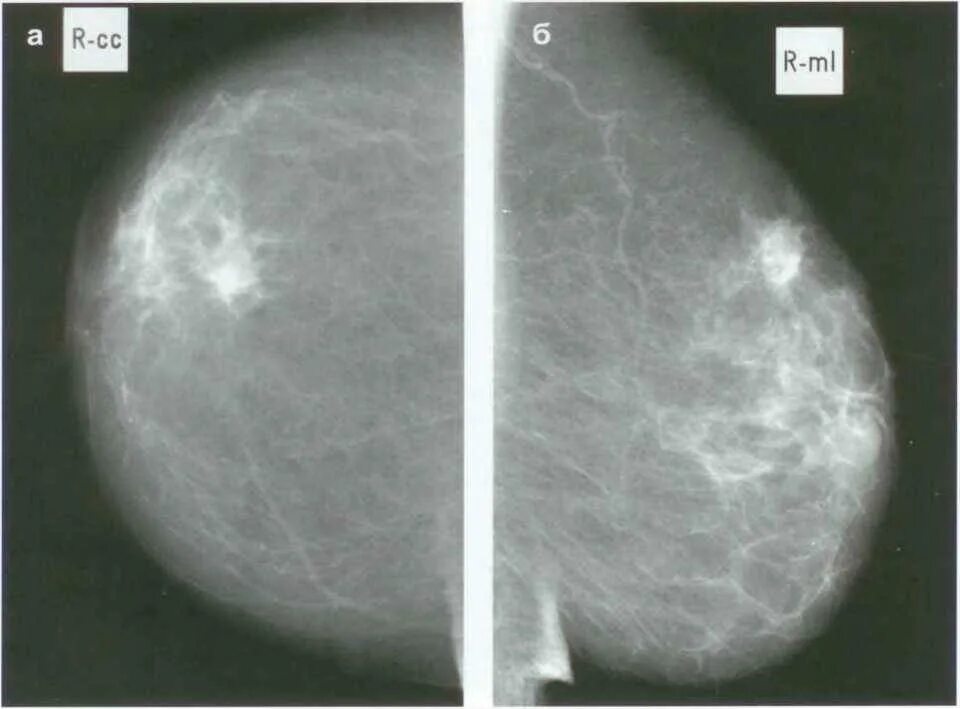

Фиброаденоматоз рентген маммография. узловая мастопатия маммограмма. протоковая карцинома молочной железы. болезнь педжета маммография.

Узловая мастопатия на маммографии. фиброаденома молочной железы маммография. кистозная мастопатия маммография. диффузный фиброаденоз.

Фиброаденома на маммографии. фиброаденома молочной железы маммография. фибролипома маммография. листовидная фиброаденома на маммографии.

Фиброаденома молочной железы маммография. инволютивная фиброаденома молочной железы. фиброаденома при маммографии. маммография молочных желез фиброаденома.